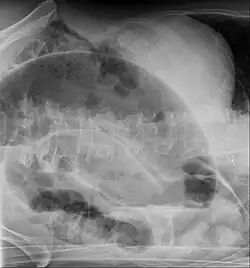

Volvulus with gangrene of the sigmoid